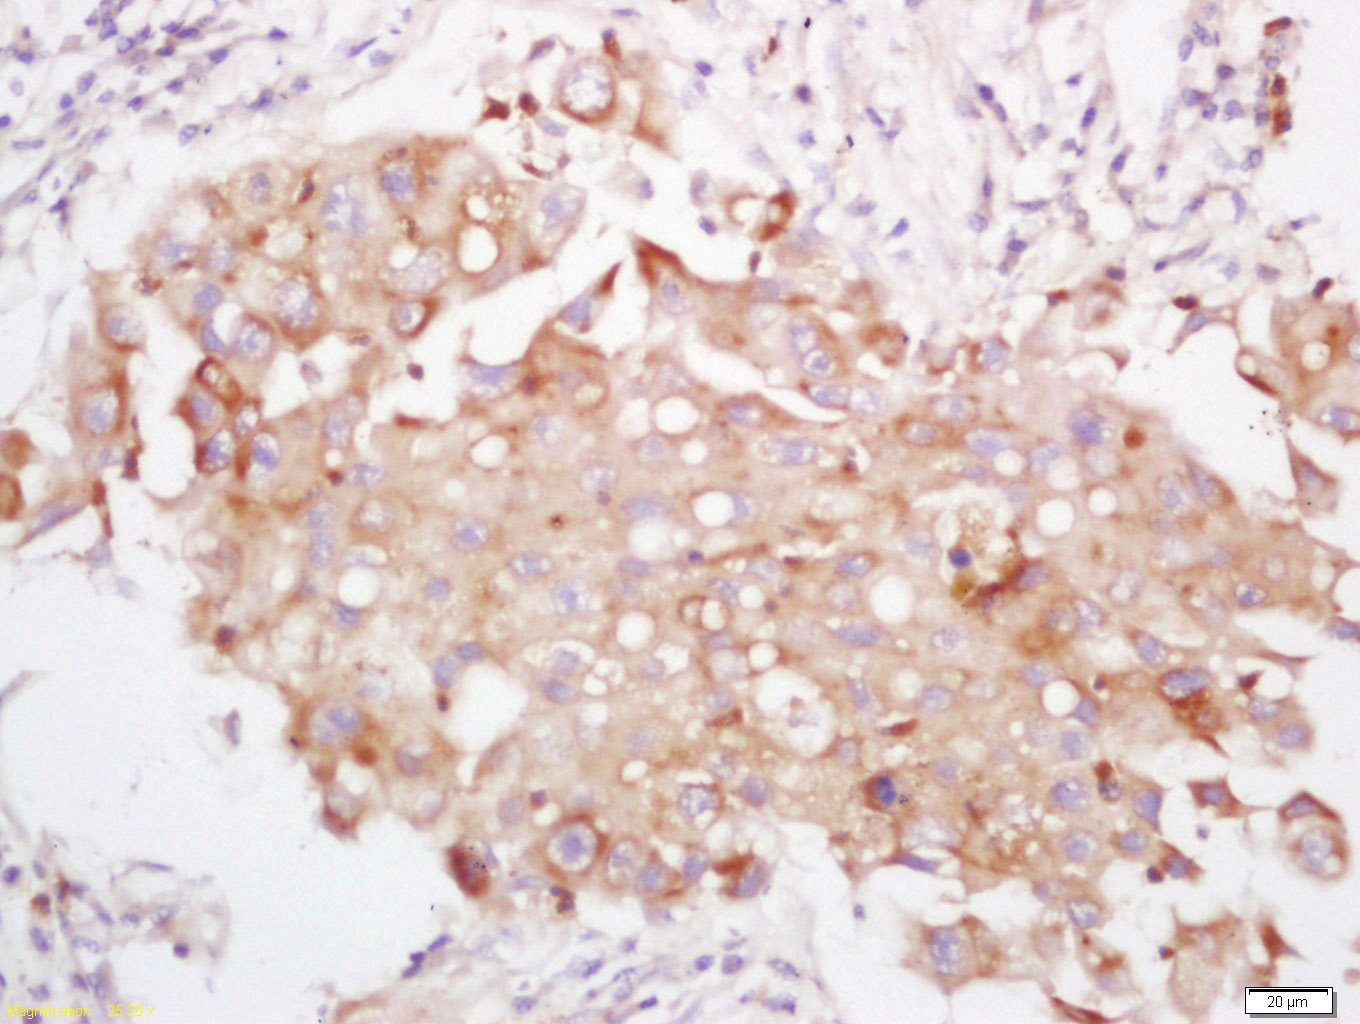

Tissue/cell: human lung carcinoma; 4% Paraformaldehyde-fixed and paraffin-embedded; Antigen retrieval: citrate buffer ( 0.01M, pH 6.0 ), Boiling bathing for 15min; Block endogenous peroxidase by 3% Hydrogen peroxide for 30min; Blocking buffer (normal goat serum,C-0005) at 37℃ for 20 min; Incubation: Anti-PI3 Kinase p110 delta Polyclonal Antibody, Unconjugated(bs-10656R) 1:200, overnight at 4°C, followed by conjugation to the secondary antibody(SP-0023) and DAB(C-0010) staining